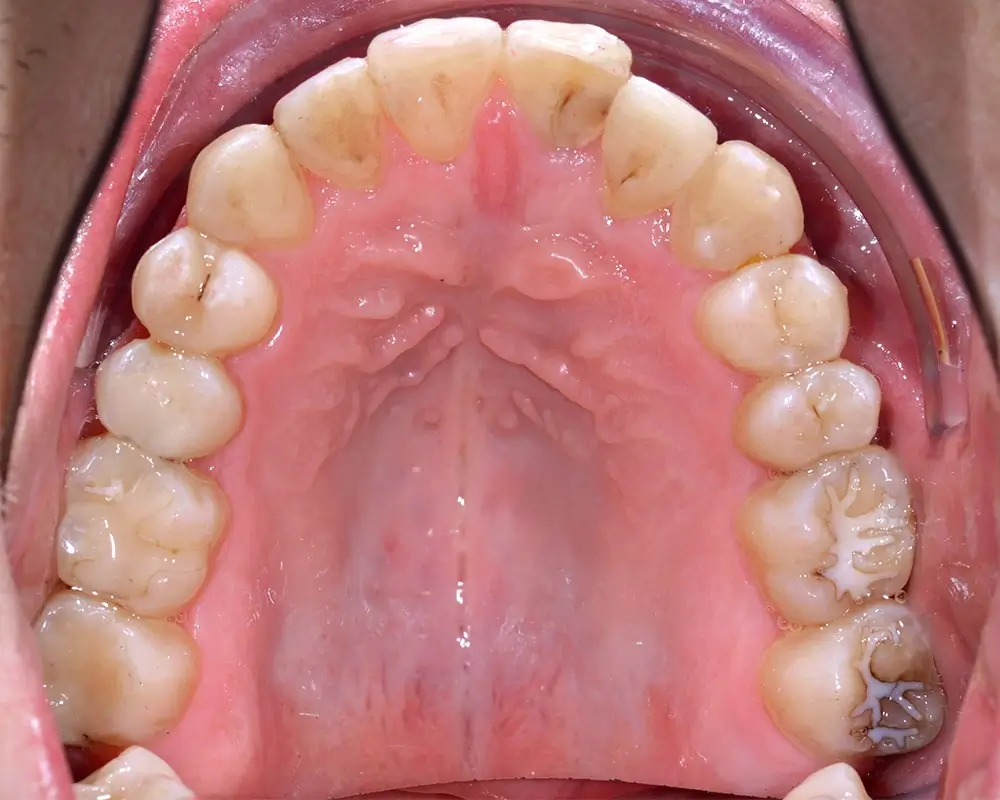

Кейс 4

Бажанова Ольга Валерьевна

Количество кап ВЧ 35

Количество кап НЧ 35

ДО

ПОСЛЕ